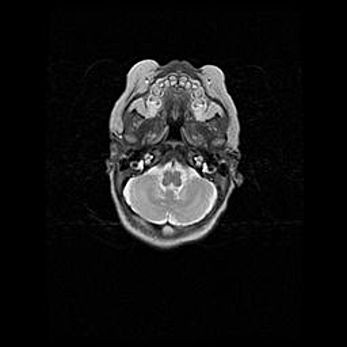

Ниже представлена  галерея МРТ снимков, полученных с применением LMT неонатальных матричных РЧ катушек. Также каждая группа МРТ снимков сопровождается информацией о пациенте (диагноз, возраст, вес, пол, срок гестации) и краткой сопроводительной расшифровкой диагноза.

Подострая гематома правой гемисферы мозжечка.

Наружная гидроцефалия.

Возраст: 15 дней

Вес: 3100 г

Пол: женский

Окружность головы: 37 см

Срок гестации: 35-36 недель

При открытой наружной форме гидроцефалии у новорожденных расширяются и переполняются субарахноидные пространства.

Кровоизлияния в мозжечок имеют две клинико-анатомические формы: полушарные гематомы и кровоизлияния в червь.

К появлению этой патологии может привести: повреждения головного мозга, возникающие в результате асфиксии и гипоксии плода при беременности, или травмы во время родов. Редко гематома мозжечка может быть результатом первичной коагулопатии и сосудистой мальформации, диссеминированном внутрисосудистом свертывании, изоиммунной тромбоцитопении.